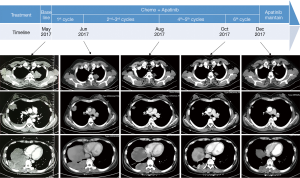

The patient refused to receive imatinib due to excessive expense of the targeted medication. She then received combined chemotherapy with ifosfamide, cisplatin and apatinib (ifosfamide 1,600 mg/m2 intravenously on days 1 to 5, cisplatin 25 mg/m2 intravenously on days 1 to 3, and apatinib 500 mg daily oral administration on days 1 to 14, every 3 weeks). After 6 courses of treatment she felt relieved from her shortness of breath and cough; a chest CT scan showed that a remarkable partial response was achieved (Figure 3). Later, maintenance therapy with apatinib alone (500 mg, daily oral administration on days 1 to 14, every 3 weeks) was given. The patient is under a stable condition at the time of writing.